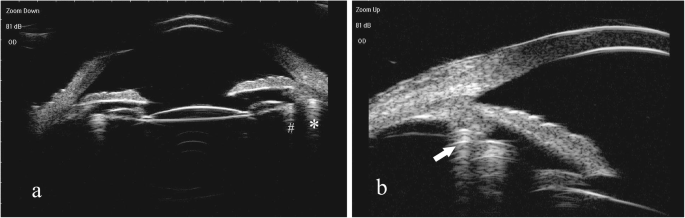

All patients had a single cyclodialysis cleft (Fig. 2a & b). The extent of the cyclodialysis cleft was 2.9 ± 1.4 clock hours (range 0.5–6.5), and most of the patients (90%) had a large cleft (≥ 1.5 clock hour). The location of the cleft varied and the cleft affected one quadrant (3 clock hours) in 14 patients, one to two quadrants (3 to 6 clock hours) in five patients, and three quadrants (> 6 clock hours) in one patient.

Preoperative clinical images in representative cases of cyclodialysis cleft and zonular dialysis. a & b Preoperative ultrasound biomicroscopy image showing cyclodialysis cleft and zonular dialysis for the same patients. c Preoperative B-scan ultrasonographic image showing the detachment of choroid. d Preoperative slit-lamp biomicroscopic photograph showing temporal iridodialysis, zonular disruption with a subluxated lens, and a posterior subcapsular cataract

Postoperative ultrasound biomicroscopy images of dual capsular tension rings insertion in the ciliary sulcus and the capsule. a & b Ultrasound biomicroscopy showing a double indentation sign (arrow) after inserting a Cionni-modified capsular tension ring in the ciliary sulcus and a capsular tension ring in the capsular bag. The two arc-shaped strong echoes with multiple reflections on the picture indicate the Cionni-modified capsular tension ring (*) and the capsular tension ring (#) (The two pictures below are taken from the same patient)